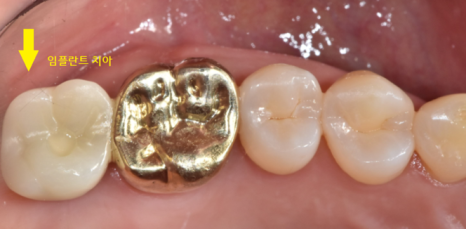

240213

그 이후 과정은 같습니다.

임플란트와 뼈가 단단하게 붙으면

기둥을 세우고 머리를 제작

240318

어금니 뿌리 쪼개짐으로 발치하셨지만

튼튼하게 사용하실 수 있도록

임플란트 심어드렸습니다!!